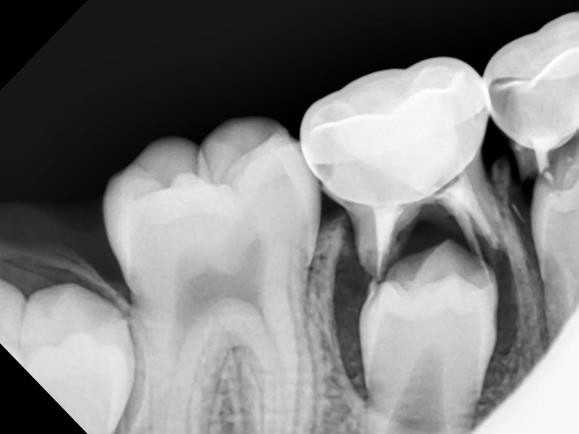

Dental sealants are thin, plastic coatings that seal over the narrow grooves found on the chewing surfaces of back teeth (molars and premolars).

When placed perfectly on these deep pits, sealants can prevent a significant amount of tooth decay (cavities) by protecting sensitive tooth surfaces from acid that causes cavities.

Dental sealants function much like sealing cracks in a driveway or on the sidewalk. The grooves in the chewing surfaces of back teeth are sealed so that food particles and bacteria will not settle within the fissures, causing cavities.